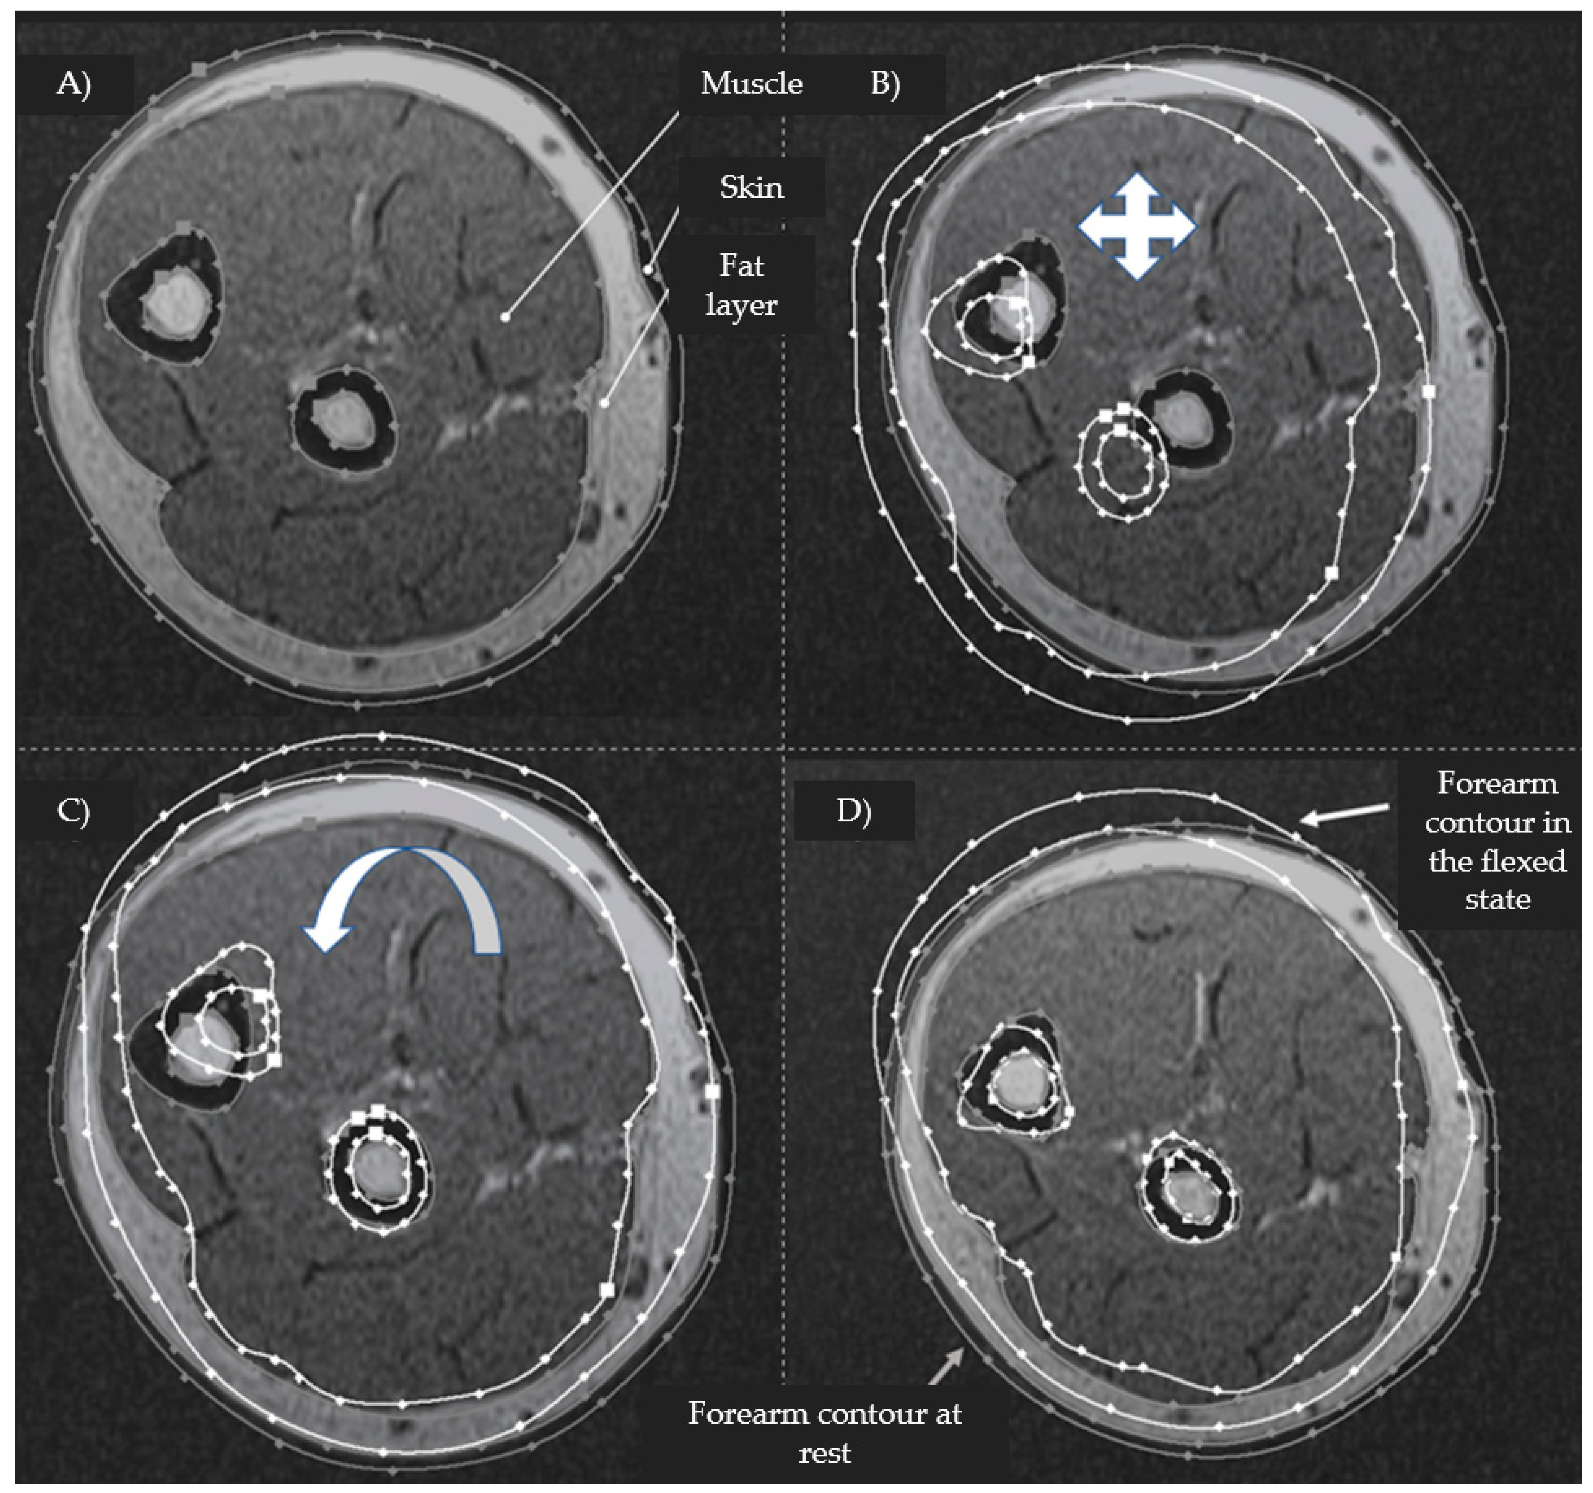

2.4. Parametric Assessment of Morphological Changes in Forearm Tissues When Performing Hand Actions Based on MRI

3.1. Study of Morphofunctional Activity of the Forearm Muscles When Performing Actions